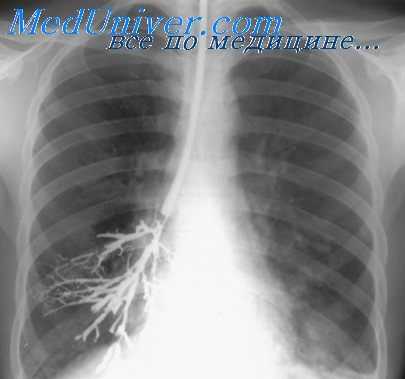

Заполнение бронхов контрастным веществом при исследовании больного на трохоскопе производится, как и при обычной методике, после поворота больного на бок. Однако в данном случае нет необходимости применять боковую бронхограмму, располагая рентгеновскую пленку с противоположной исследуемой стороны.

Надувные манжетки, изолирующие дыхательные пути каждого легкого, исключают затекание контрастного вещества во время исследования в бронхи второго легкого. Благодаря этому, заполнив бронхи нижележащего легкого, мы поворачиваем больного на спину и производим бронхографию в прямой проекции. Затем под контролем экрана совершаем поворот больного в боковое положение, при котором исследуемое легкое становится вышележащим, то есть максимально приближенным к рентгеновской пленке. В этом положении осуществляют боковую бронхограмму.

30 больным, исследованным по данной методике, мы производили две боковые бронхограммы: первая — со стороны, противоположной исследуемому легкому, иначе говоря, по общепринятой методике, и вторая — со стороны исследуемого легкого.